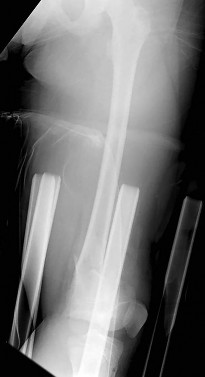

A 3-year-old boy sustains a closed, isolated, midshaft femur fracture after a fall from a playground structure.

Radiographs show 1.5 cm of overriding. What is the most widely accepted definitive management for this patient?